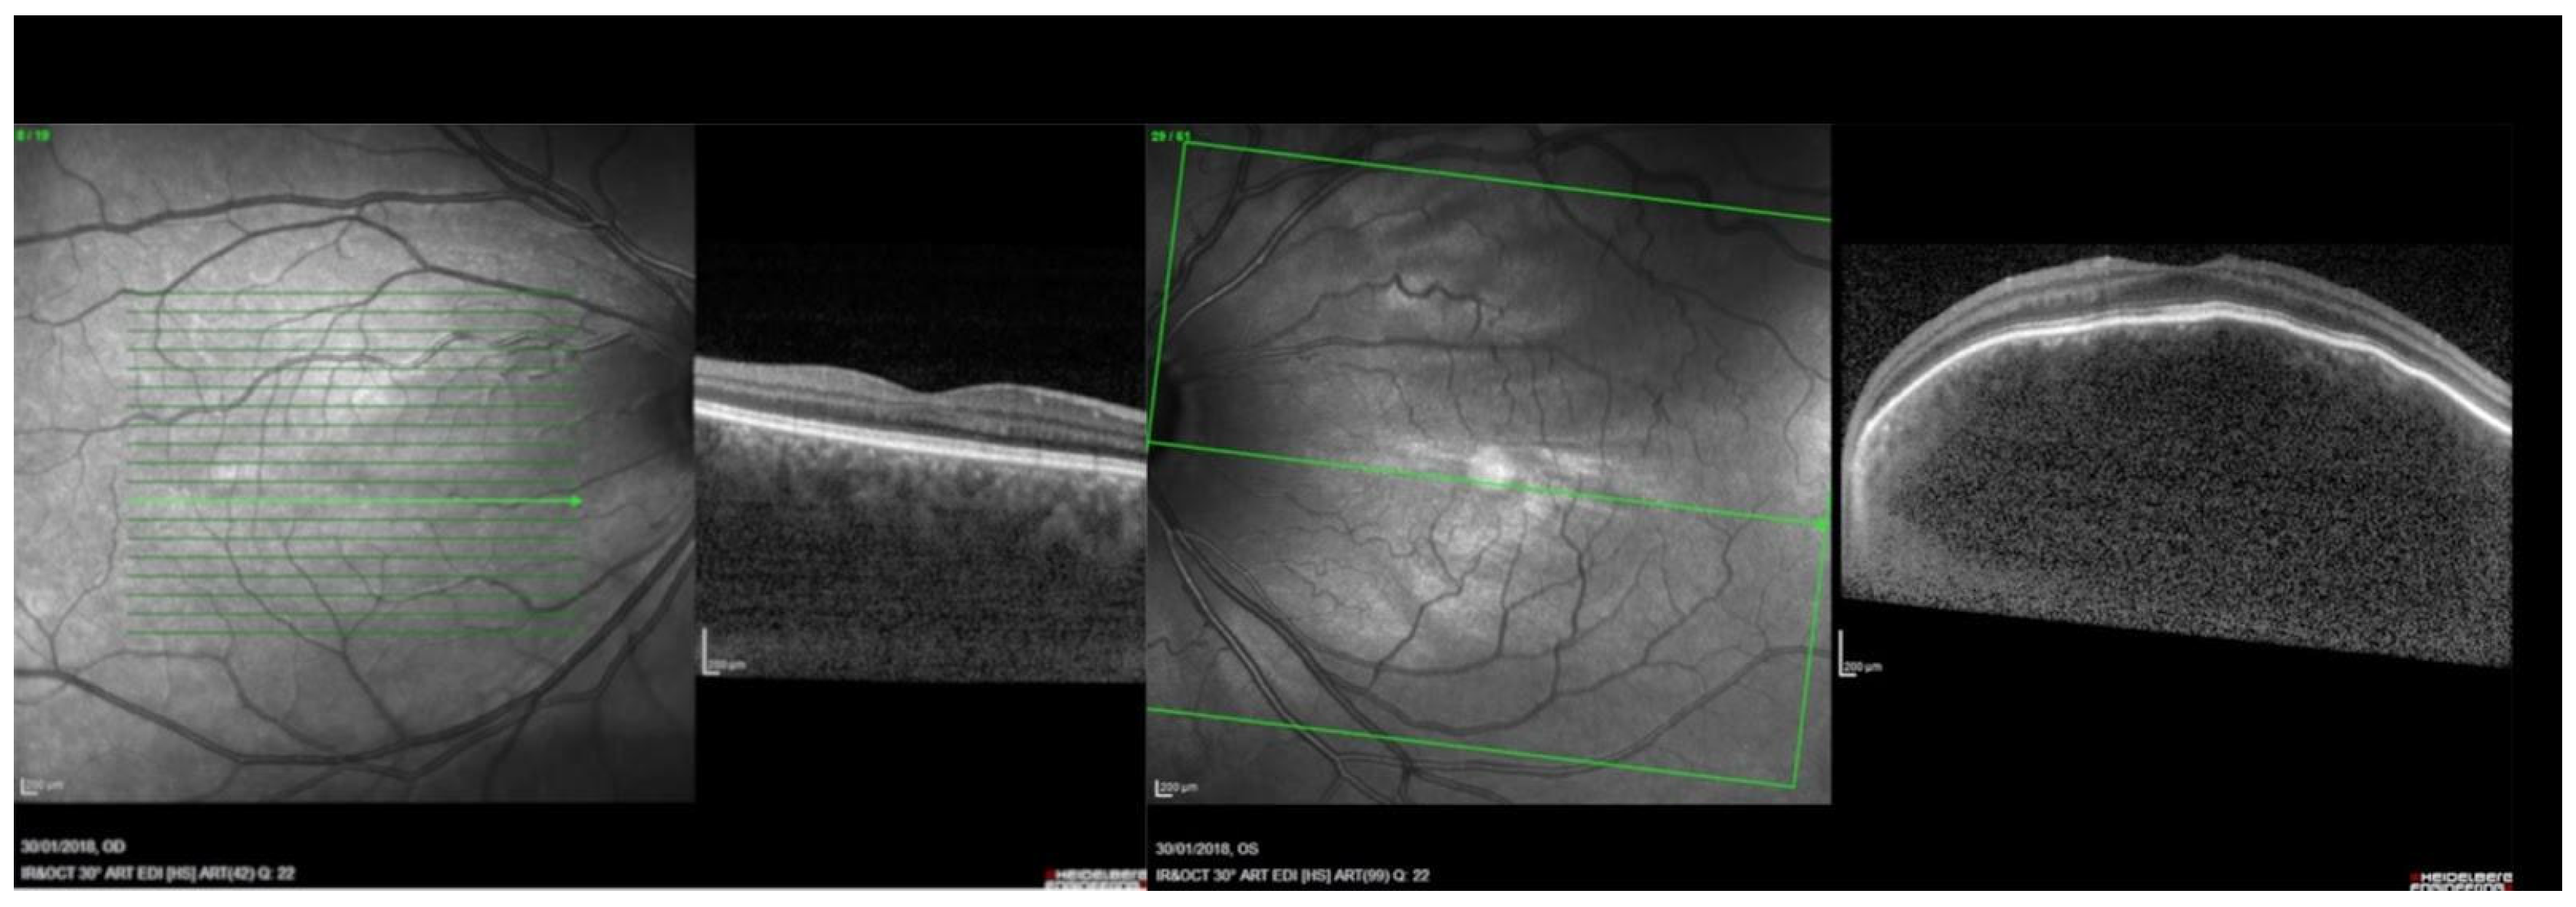

| SDOCT WL 840–870 nm [56,57,58,59]. | Efficient; non-invasive; allows for the identification of retinal layers and assessment of retinal thickness. | In cases of thickened choroid SDOCT falls short in evaluating the choroidal-scleral junction. | It can reveal the breakdown of Bruch’s membrane and RPE, intraretinal fluid, and subretinal fluid. |

| EDI-SDOCT WL 840–870 nm [56,57,58,59]. | Efficient; non-invasive; allows for a better visualization of the choroidal-scleral junction which renders manual choroidal thickness measurement easier. | Not always available in hospital settings. | Choroidal vasculature is visualized on EDI-SDOCT cross sectional images. Profile alterations of the retina and choroid are well visible. |